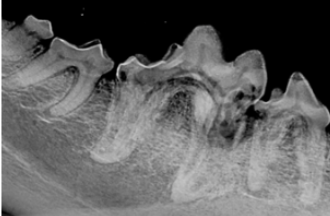

The investigational trial will evaluate the safety, efficacy, and potency of using stem cells to treat cats with refractory gingivostomatitis.

Test your diagnostic skills by examining the following images and selecting the answer you think fits best.